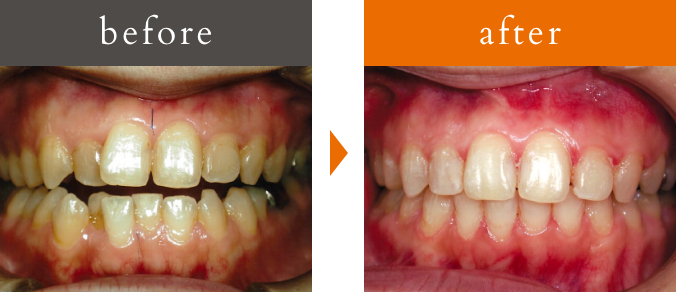

八重歯・ガタガタ

治療概要

主訴:八重歯・歯のガタつき・顎の不調和による噛み合わせの乱れ

治療内容:3D-LST矯正治療法を用い適切に歯を移動。見た目だけでなく、噛みやすさや顎の安定感も向上

患者年代・治療期間

20代女性・1年9ヶ月